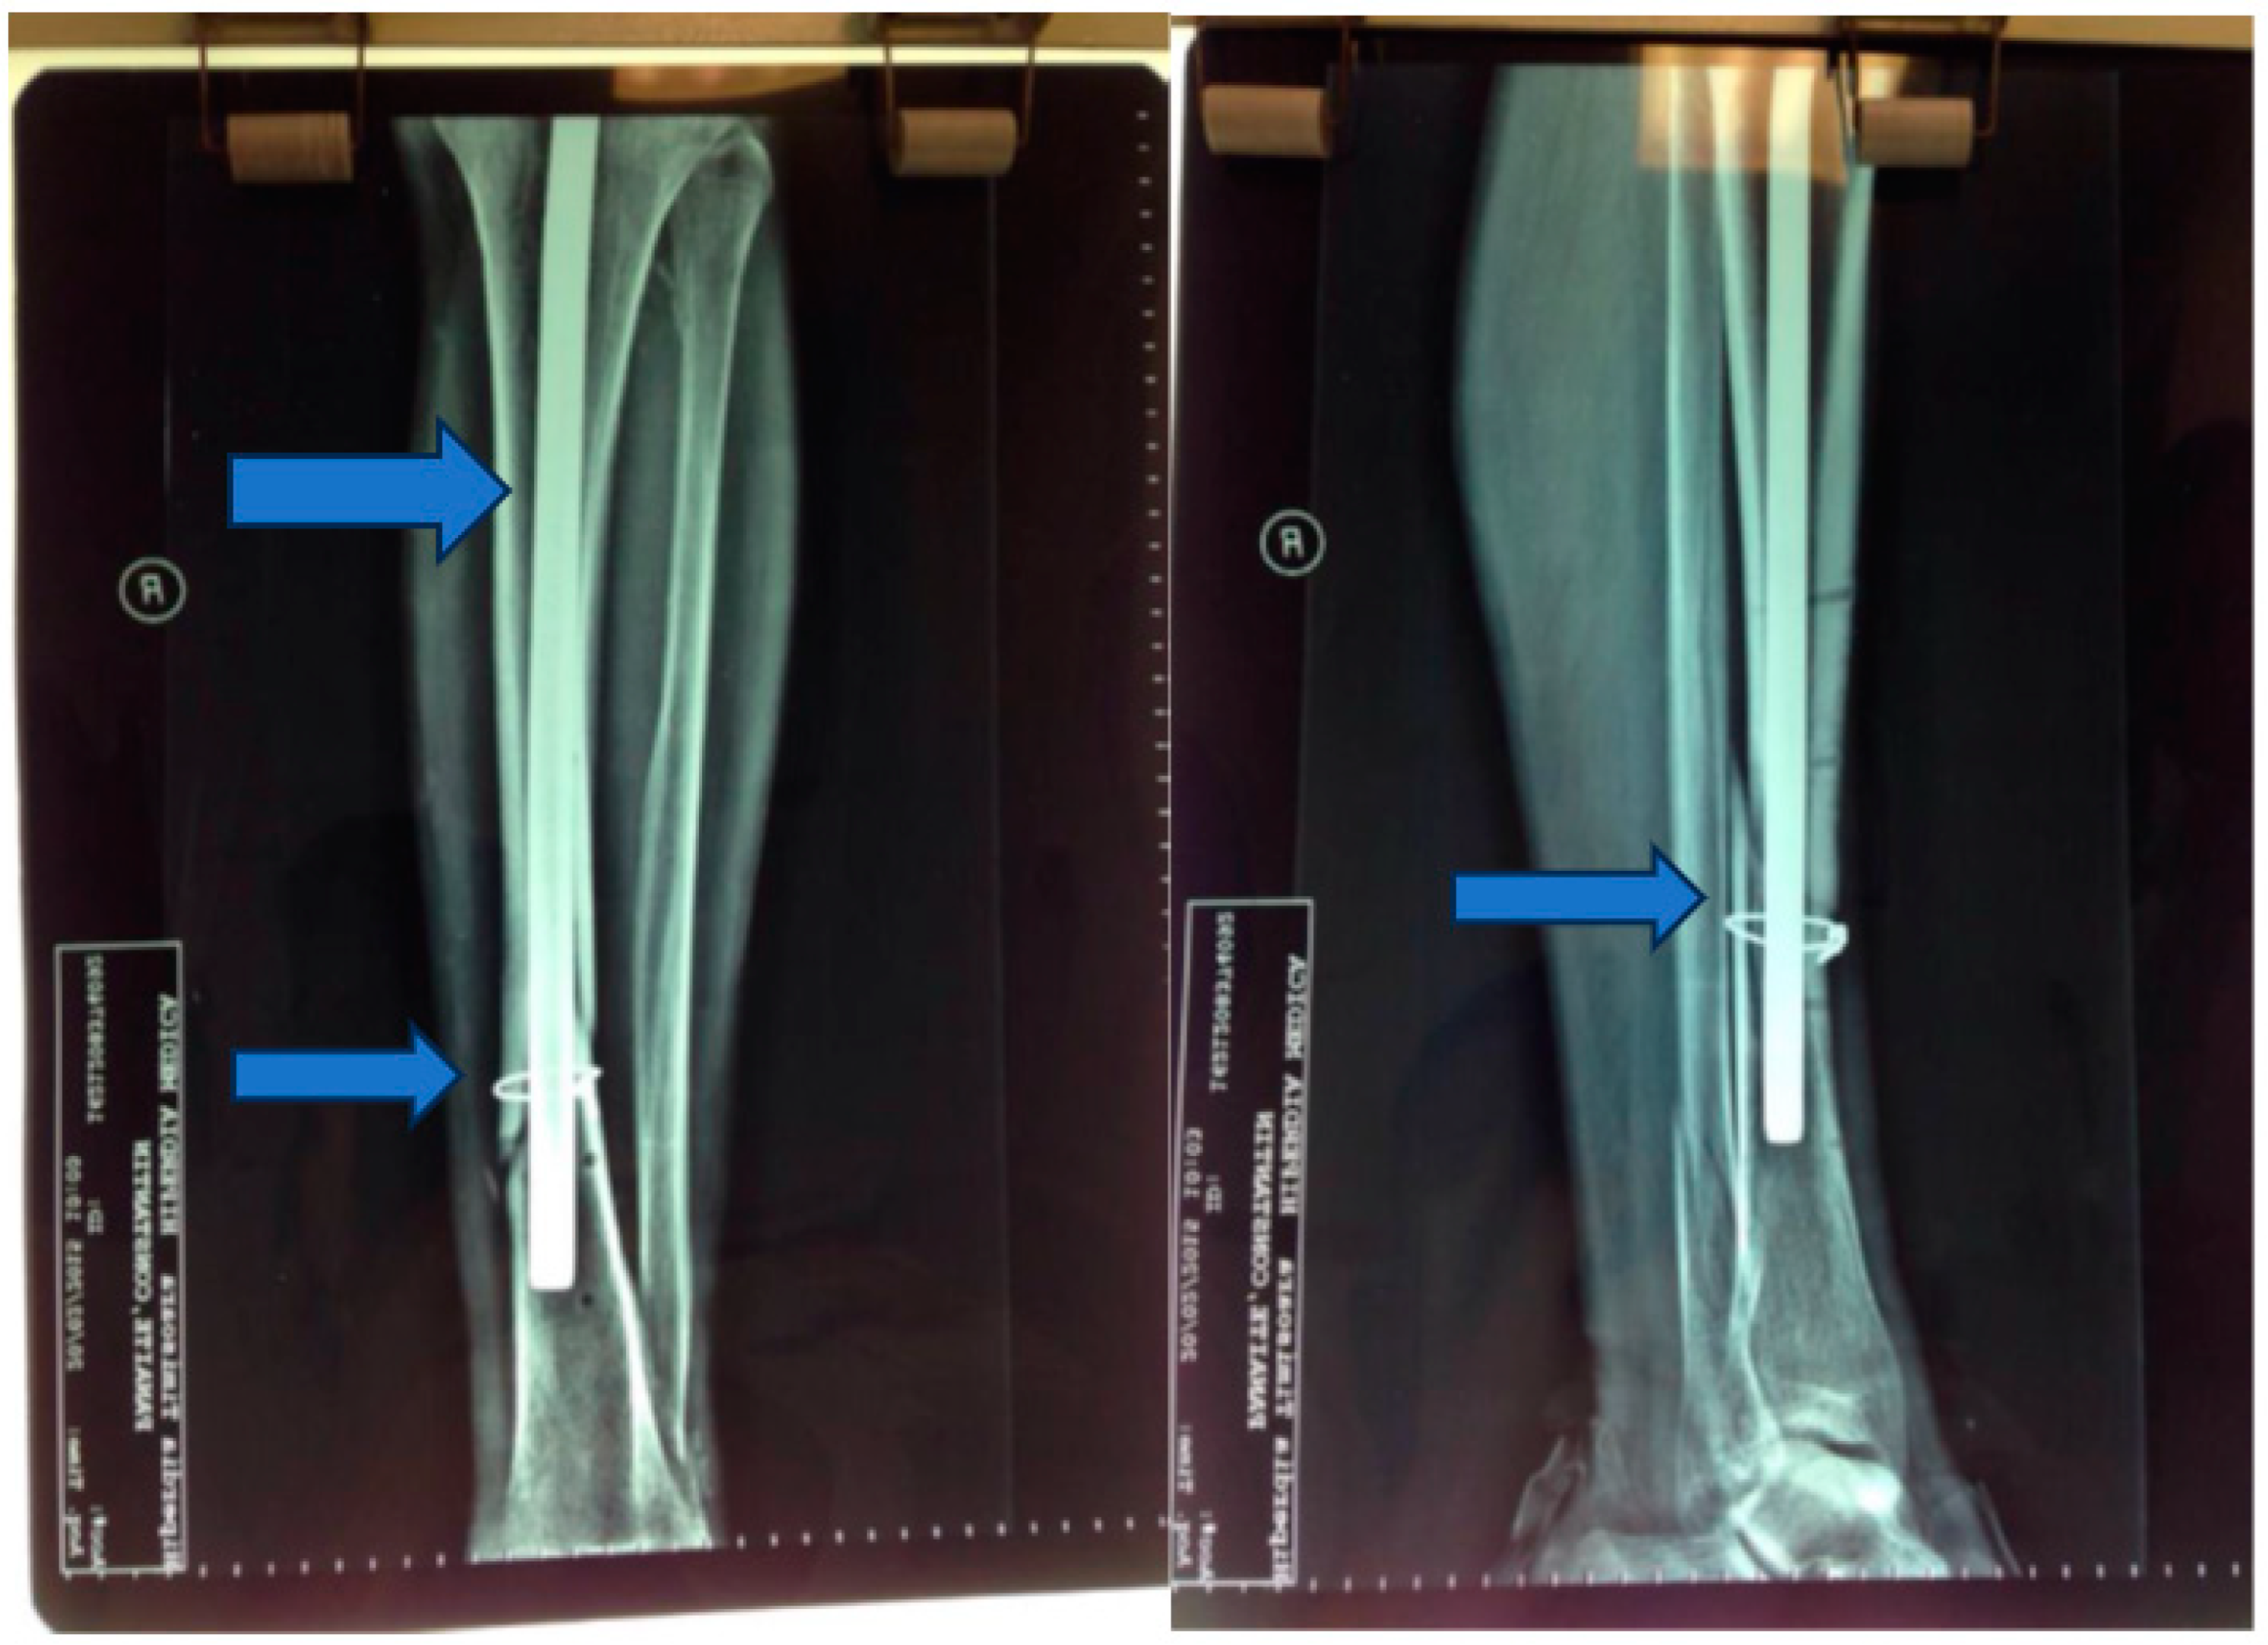

Seven days postinjury, an osteosynthesis procedure was performed, involving the placement of a Kuntscher nail and wire cerclage (Figure 2 and Figure 3).

Figure 2. Kuntscher nail and wire cerclage.

Jpm 13 01651 g002

Figure 3. Postoperative X-ray—2 months.

Jpm 13 01651 g003